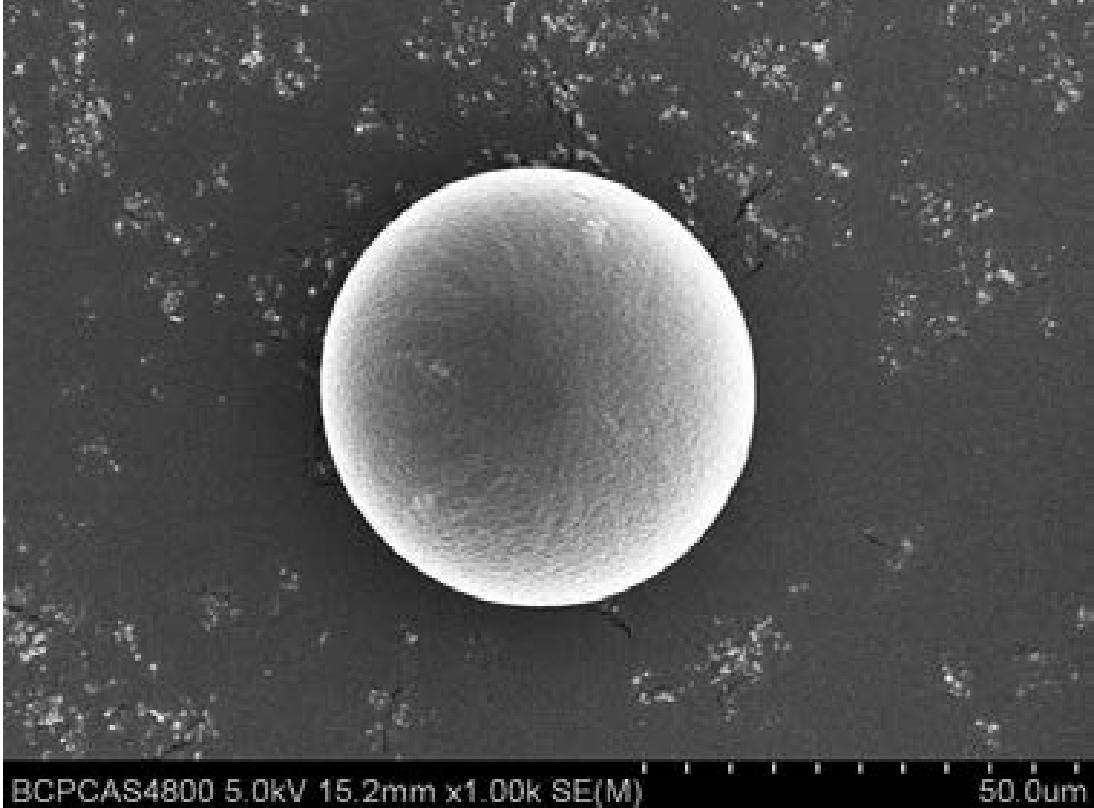

Vita Spire has developed HAp microsphere products for next-generation aesthetic fillers. We offer three different products, each varying in porosity, which corresponds to different degradation rates after injection. Our HAp microspheres provide versatile options for creating specialized, high-quality aesthetic treatments.

| Image | Cat. No. | Product Name | Features | Action |

|---|---|---|---|---|

| HAPAI-01 | Hydroxyapatite (HAp) Microspheres for Aesthetic Injection, Type I | N/A | Details |

| HAPAI-02 | Hydroxyapatite (HAp) Microspheres for Aesthetic Injection, Type II | N/A | Details |

| HAPAI-03 | Hydroxyapatite (HAp) Microspheres for Aesthetic Injection, Type III | N/A | Details |